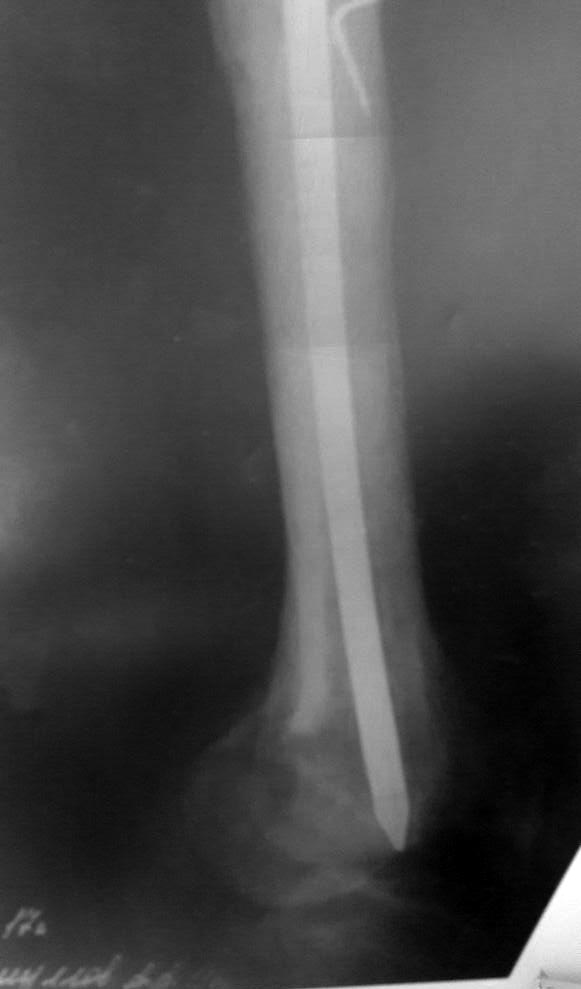

Доброго дня коллеги!поступает пациент, оперирован 9 лет назад,

последний месяц начали беспокоить боли в коленном суставе при ходьбе

последний месяц начали беспокоить боли в коленном суставе при

ходьбе!Визуально отек коленного сустава,синовит, ограничение и сгибания

и разгибания. наш план зайти антеградно при помощи эопа и всетаки

попытаться его удалить. Сейчас ищем инструмент через москву. на потоке

это никогда не ставили. хотелось бы услышать мнения, советы.